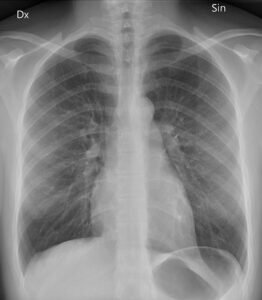

Th next lesson is a deep dive into the pathophysiology of diseases affecting our lungs. Here we reinforce an appreciation of what the body needs to sustain itself in health, and what processes unfold when imbalance is sustained beyond the capacity to buffer and equilibrate. We start by contemplating the story of Tobacco and its use in Native America and the modern world. Attention is then turned to each of the big categories of ailments affecting the respiratory system; chronic bronchitis, emphysema, pulmonary fibrosis and hypertension, pneumonias and tuberculosis (TB), lung cancer, and cystic fibrosis. For each condition the underlying causes and manifestations in the histopathology, as well as clinical symptoms and signs are explored.